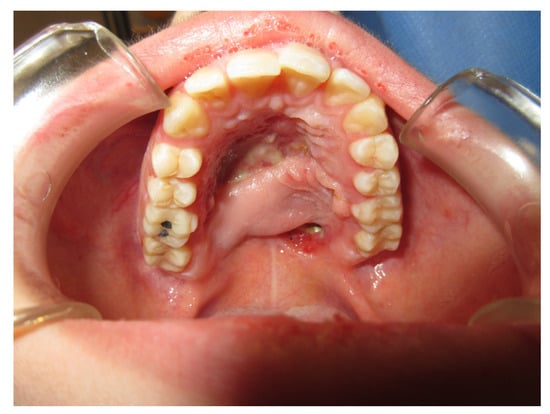

3.1.3. Case 3: R.M.

| R.M. | X | * | 9 | 0 | ||